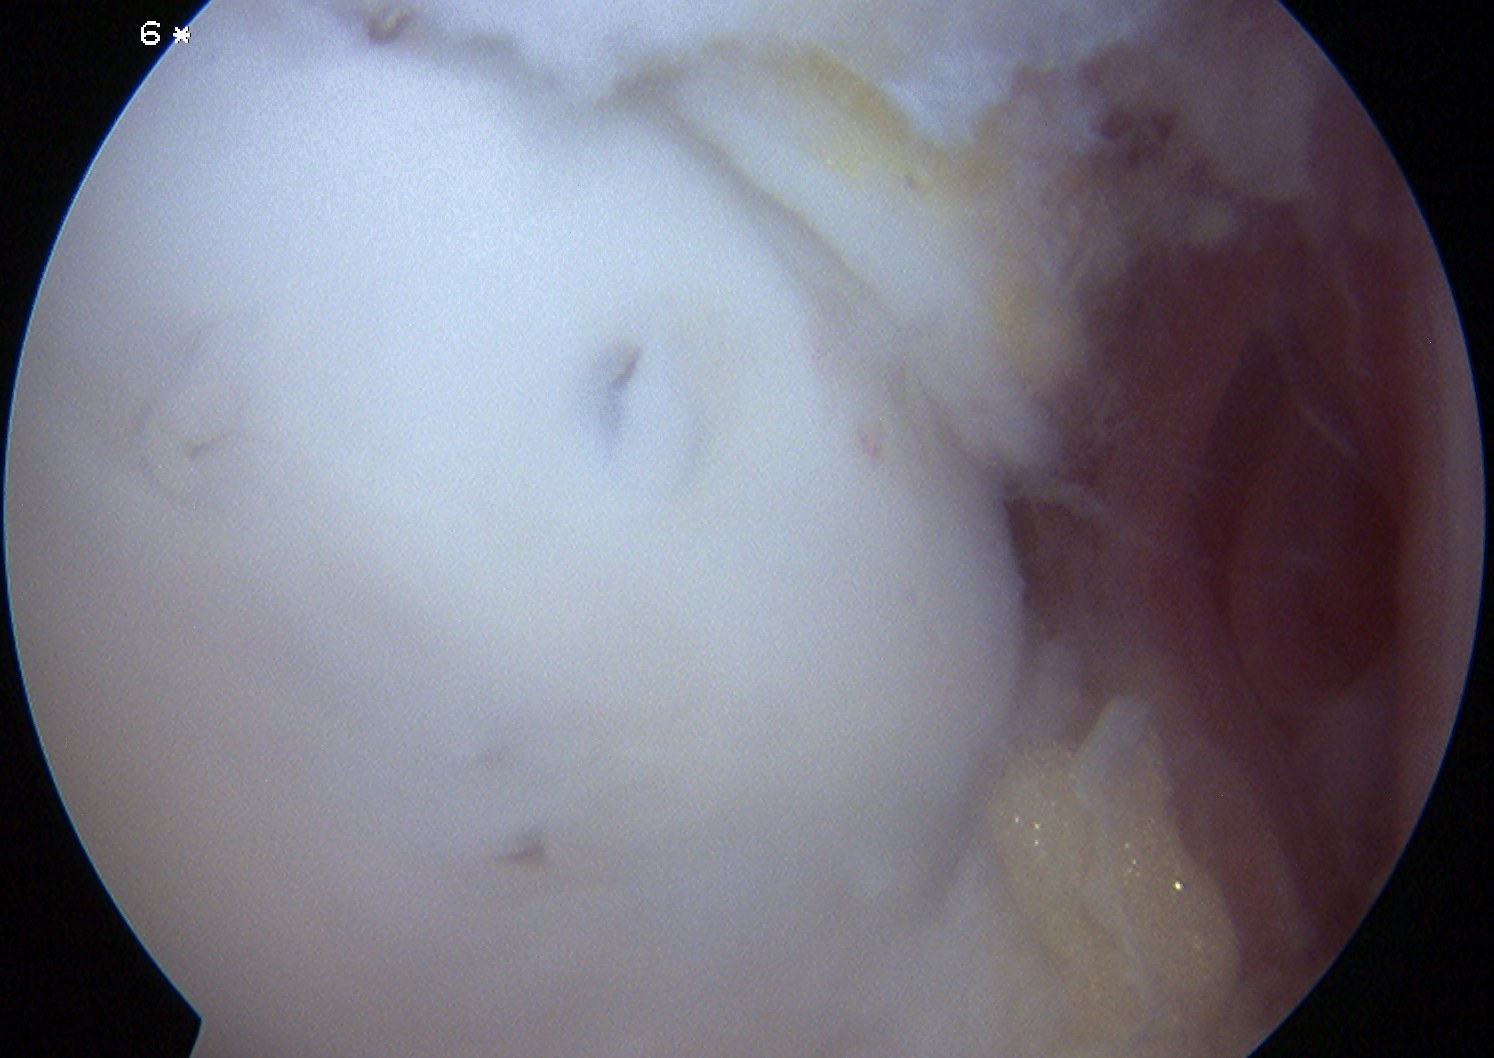

Arthroscopy Approaches

Anterolateral / anteromedial

- anterior 50 - 60% lesions

Anterolateral osteochondral lesion accessible via plantarflexing the ankle